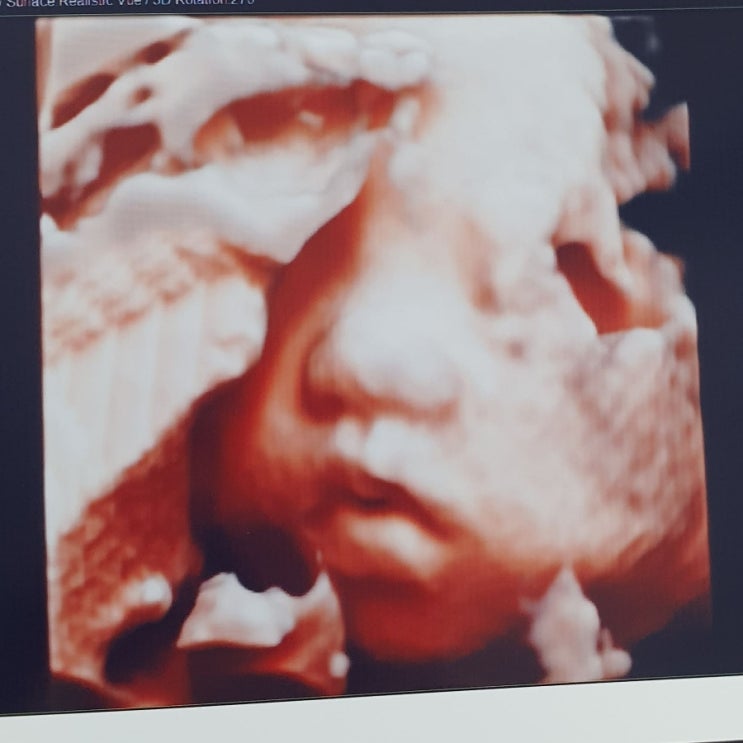

[임신일기] 임신성당뇨ㅜㅜ 임당재검과정

안녕하세요. 송송, 달콩 맘이에요 ㅎㅎ 임신을 하게되면 수많은 검사를 거치게 되죠. 제가 생각하는 검사의...

[임신일기] 늦은 임밍아웃과.. 노산맘이야기 시작해요 ㅋㅋ

저희집에 새생명이 찾아왔어요 ㅎㅎ 블로그에는 너무 늦은 임밍아웃이네요 ^^; 저희 가족은 송송이가 3살될...